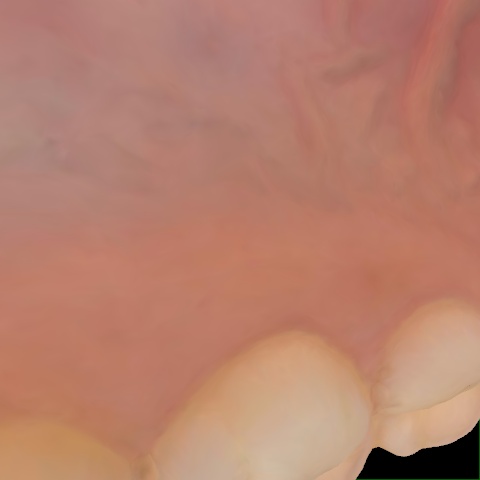

Incorrect Quality Level

The reference annotation for this image is

None

.

Please select the correct quality level.

Annotated as "Good"